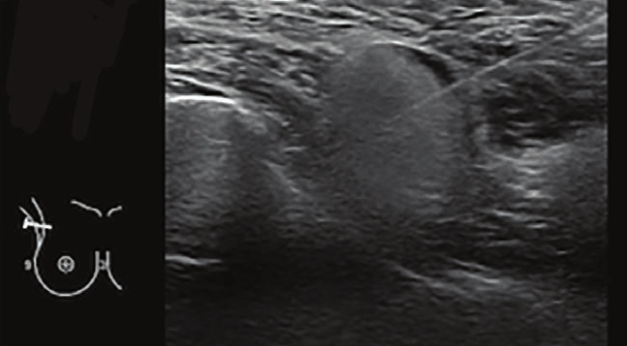

雅得媚饅化的超音波影像

雅得媚饅化在超音波下,中央呈現混濁、流動性的黑色囊腔,黑色區域周圍的邊界是一層明顯變厚的高回音纖維化包膜,顯示它被組織包覆,形成了偽囊腫或結節。